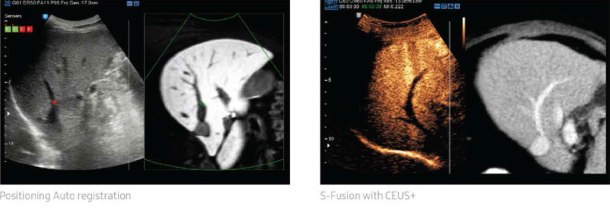

S-Fusion

S-Fusion enables simultaneous localization of a lesion using real-time ultrasound in conjunction with other 3D volumetric imaging modalities. Where the image fusion method faces challenges such as relatively slow and inaccurate registration, Samsung offers a quicker and more precise registration process. S-Fusion allows precise targeting during interventional procedures. With S-Fusion, your system is ready for many advanced clinical procedures.

Respiration Auto

When performing fusion imaging of real-time US and previously recorded CT images, the difference of respiratory phase can cause registration gaps between the images. Samsung’s Respiration Auto feature minimizes these registration differences by generating a CT image of exhalation based on the acquired image of inhalation. This respiration compensation technology makes the registration faster, helping eliminate fusion inaccuracy.